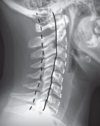

66

Las fracturas cervicales son detectables en: | ¿Cómo se toma?

Rx - AP boca abierta - Lateral - Valorar 3 líneas cervicales

67

Mejor método de imagen para fracturas cervicales

TC